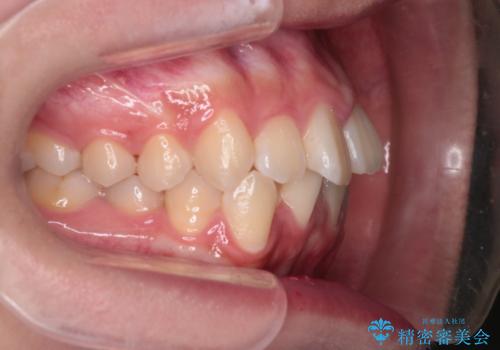

【インビザライン】前歯の凸凹を非抜歯で治療

- 前歯の凸凹を主訴の来院されました。

奥歯を後ろの方に移動させるために矯正用のアンカースクリューを使いながら治療をおこないました。

患者さんの都合により、マウスピースの装着時間が不足したため、途中からワイヤーにて治療を行いました。